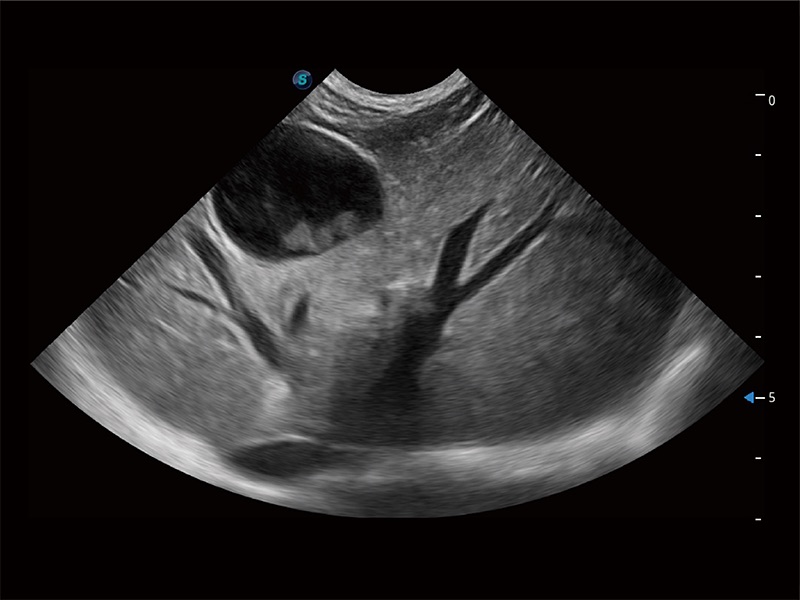

动物是人类最亲密的朋友和最值得信赖的伙伴。银河优越会也一直致力于探索动物专用的超声影像解决方案。全新推出的ProPet系列,是银河优越会在动物超声影像智能化、专业化、精准化的一次跨越式革新。动物不能用言语来表述自己的不适,通过超声影像,ProPet系列搭建了动物医生与不同物种沟通的“桥梁”,为动物医生注入了“治愈之力”。 ProPet 80 是银河优越会匠心打造的一款高端动物专用彩超,采用性能卓越的全新硬件架构,极大提升超声系统的运行效率和数据处理能力,帮助动物医生从容应对日益增多的挑战性病例和日益多样化的临床需求。

高性能和先进的临床应用工具可以为动物医生提供临床信心。ProPet 80 搭载了先进的腹部和浅表应用工具,帮助医生在日常临床实践中发挥前所未有的作用。

ProPet 80 全新的动物超声智能软件和丰富的探头群,为动物医生提供了高清晰度和精细分辨率的图像,无论在宠物、马科、畜牧还是实验室动物等应用中都可以轻松应对,为您的日常工作带来满意的体验。